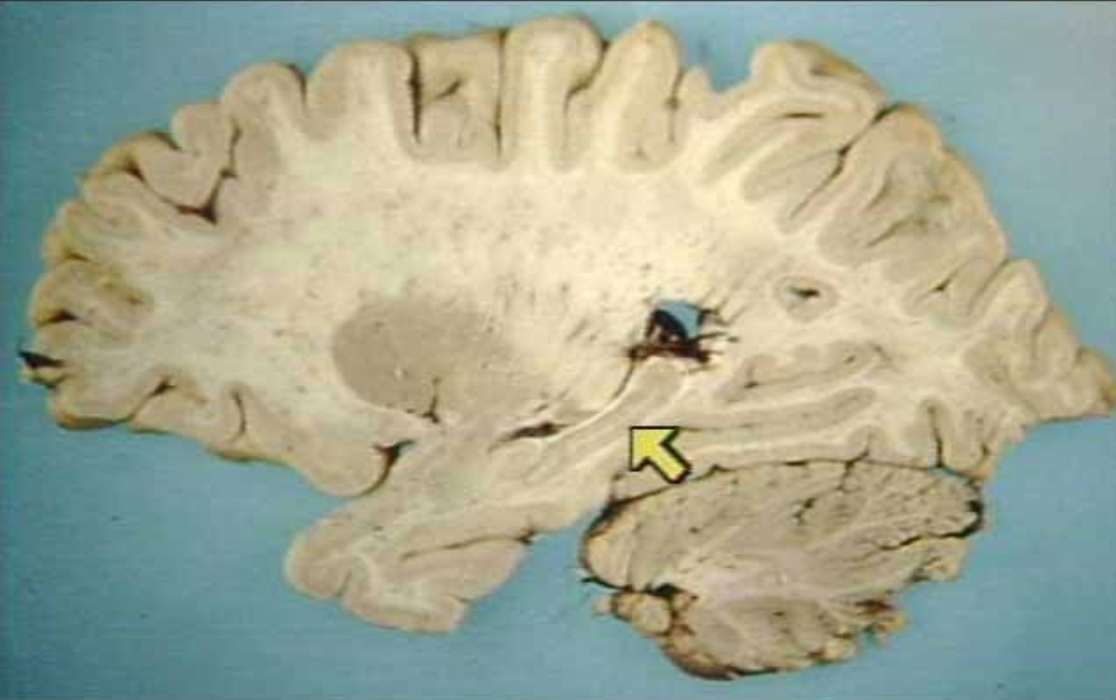

What is the arrow pointing at?

Amygdala